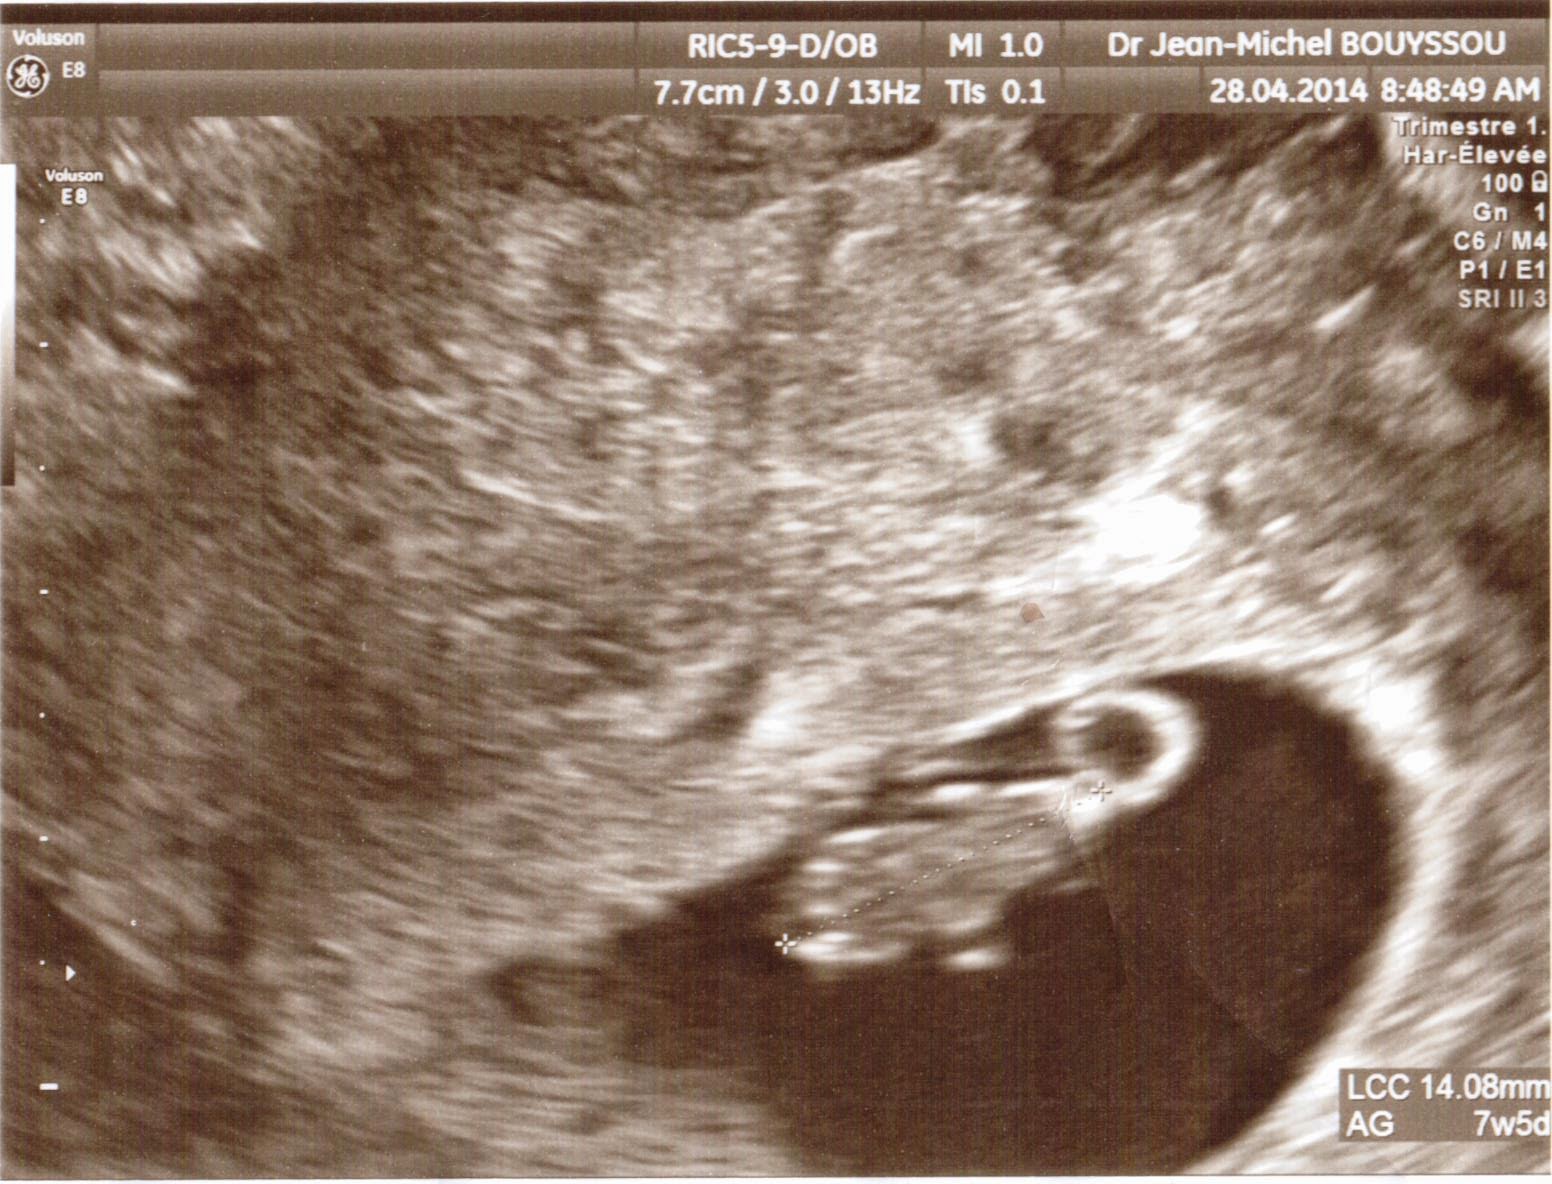

L'épiderme commence sa formation.Votre utérus a désormais la taille d'une mandarine.Découvrez ce qui vous attend de palpitant maintenant que vous êtes à 6 semaines de grossesse, soit 8 semaines d'aménorrhée ! La croissance de votre bébé : un guide complet du développement du fœtus à 6 semaines. Il mesure entre 10 et 15 mm pour un poids d'environ 1,5 g.; Il a une tête proéminente et la forme d'un haricot

6 semaines de grossesse quelles sont les différentes choses à savoir. Une grosse tête et des gouvernails en guise de bras ! Votre bébé a énormément grandi et votre utérus aussi ! Même si l'on ne voit pas encore grand-chose, il se passe beaucoup de choses au cours de la 6 ème semaine de grossesse A 1 mois et demi de grossesse, les symptômes de grossesse sont encore bien présents et votre corps se transforme petit à petit

6ème semaine de grossesse 8 SA tout savoir May app. À la 6e semaine de grossesse, découvrez l'apparence du foetus, les changements corporels et les aliments recommandés. Découvrez ici les étapes importantes de la 6 ème semaine et réjouissez-vous, car à partir de maintenant, vous entendrez systématiquement le battement.